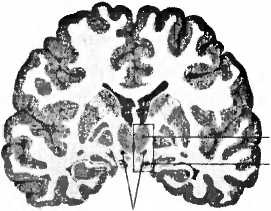

Рис. 22. Пациенту с болезнью Паркинсона имплантирован электрод (Е) в нужное место в субталамическом ядре (nucleus subthalamicus). Т — таламус; ТО — tractus opticus (зрительный тракт).

В настоящее время в мире примерно 35 000 человек живут с имплантированным в мозг электродом. Как во всякой действенной терапии, здесь тоже возможны побочные действия. В процессе социальных контактов с партнером или среди рабочего окружения люди с болезнью Паркинсона, которым имплантирован электрод, могут сталкиваться с затруднениями. Хотя большинство пациентов были очень довольны качеством своей жизни, их семьи сообщали, что иногда они делались более возбудимыми и эмоционально неустойчивыми. У 9 % были отмечены психические осложнения: повышенная импульсивность при принятии решений или приступы плача. Стимуляция электродом может усиливать депрессию, а иногда даже приводить к самоубийству. Нам известны пациенты, у которых электроды находились в нужном месте субталамического ядра (рис. 22) и которые пытались совершить самоубийство. Десять лет тому назад неврология еще не проявляла интереса к этой взаимосвязи. Бывает, что имплантация электрода приводит к кровотечению или повреждению мозга, после чего отмечаются проявления деменции, которые исчезают, если стимулятор по-другому отрегулировать. Есть также сведения о возникновении психозов, сексуальной несдержанности и игрозависимости. Пациент, который до операции был типичным бережливым голландцем, после имплантации электрода уже больше не мог спокойно пройти мимо игрового автомата. Лишь после того, как через несколько лет он из-за громадных долгов вынужден был продать дом, его подруга хотела его оставить и он совершил попытку самоубийства, решено было обратиться к врачу. Игрозависимость может возникнуть также при классическом лечении болезни Паркинсона леводопой. Дофаминовая система (рис. 15) играет центральную роль при возникновении зависимостей. Необычное побочное действие наблюдалось у пациента, который стал покупать дома в Испании и Турции, не имея для этого средств; несмотря ни на что, он отказывался отключить стимулятор. Стимуляция глубинными электродами может иногда вызывать нарушения мышления, речи и памяти. Побочные явления психического характера, вызванные глубокой электростимуляцией электродами, всё же в основном преходящи, они хорошо поддаются лечению и их даже возможно предотвращать. Они также дают нам возможность что-то узнать о функции структур и нейронных цепей мозга при симптомах психических заболеваний, как, например, о роли дофаминовой системы при формировании зависимостей. Успех воздействия глубинных электродов при лечении болезни Паркинсона привел к тому, что сейчас их применяют при многих неврологических и психических картинах болезни: невыносимых болях, кластерных головных болях, депрессиях, страхах, мышечных спазмах, самокалечении и обсессивно-компульсивных расстройствах. В ходу исследования лечения ожирения и зависимостей с помощью глубинной имплантации электродов. Возможности приложения этого метода кажутся неисчерпаемыми. Купер о таком и не помышлял, когда в 1952 году по оплошности вызвал кровотечение мозгового сосуда.